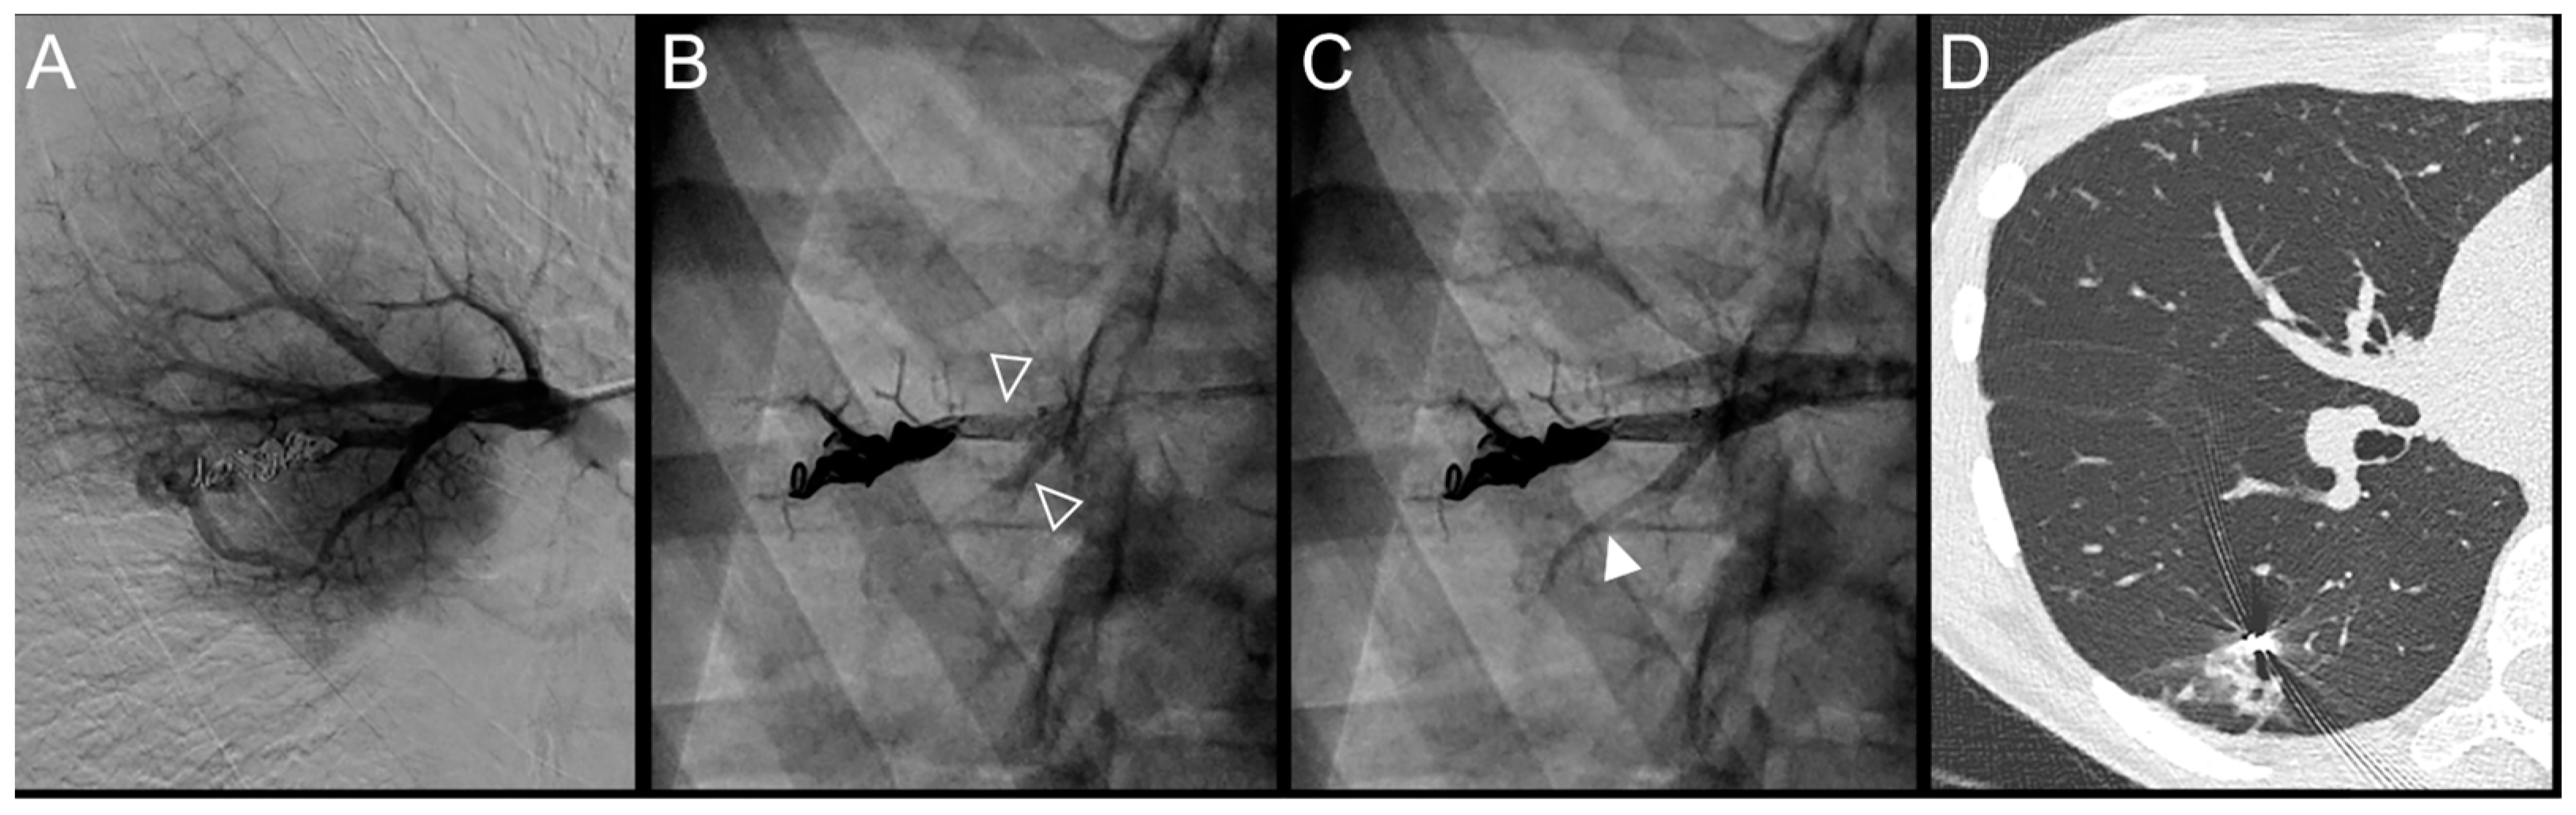

Figure 4.

Case example of an 18-year-old man treated for a complex recurrent pulmonary arteriovenous malformation in the middle lobe. Digital subtraction angiography unsubtracted images showed a recanalization in two different segmental feeder arteries (A–F). Embolization was performed using Onyx® (0.5 mL in each artery) to fill the afferent artery upstream and within the pre-implanted coiling and resulted in an immediate complete occlusion, maintained after 43 months follow-up. No leak in the aneurysm or in the vein was reported. (A). Opacification of an afferent artery (full head arrow) showed a recanalization through the pre-implanted coils. (B). Opacity upstream and in the last coil (empty arrowhead) showed the distribution of Onyx® without any evidence of a leak in the aneurysmal sac or proximal arterial branch. (C). Opacification of the afferent artery showed the absence of opacification of the aneurysmal sac and the efferent vein in favor of immediate occlusion. The opacification of the healthy arterial branch did not reveal any perfusion defect. (D). Opacification of a second afferent (full head arrow) artery showed a recanalization through the pre-implanted coils. (E). Opacity upstream of the coils showed a leak of Onyx® (empty arrowhead) without evidence of any leak in the aneurysmal sac. (F). Opacification of the afferent artery showed the absence of opacification of the aneurysmal sac and the efferent vein in favor of immediate occlusion. The opacification of the healthy arterial branch did not reveal any lung perfusion defect.